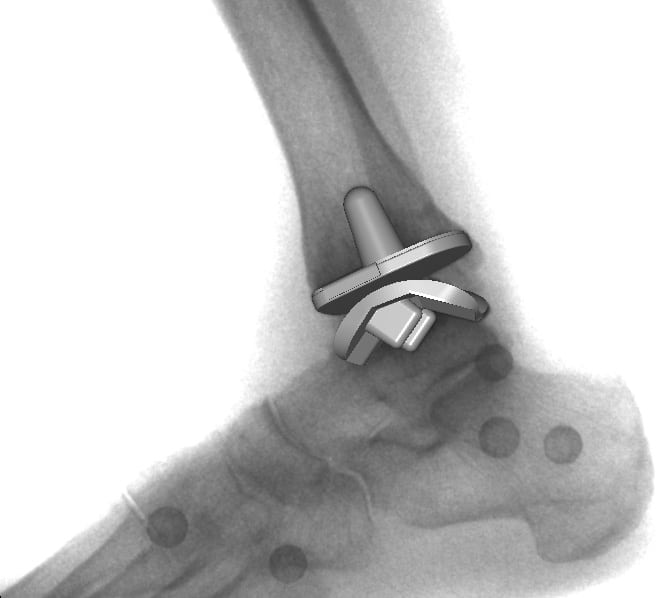

Визуальное моделирование.

Этот метод оперативного вмешательства считается щадящим, так как сохраняется значительное количество суставных структур. Раньше во время операции можно было использовать длинные стержни. Теперь пластины таранной кости фиксируют штифтами для плотного анатомического прилегания костных поверхностей с покрытием имплантата. При производстве используется специальный пористый материал, способствующий прорастанию сосудов и тканей. Это обеспечивает естественную и прочную фиксацию пластины. Для крепления нижней защитной пластины используется короткий дюбель, но сердцевина вообще не закреплена. Он предназначен для обеспечения плавного скольжения между верхней и нижней металлическими пластинами. Верхний элемент имеет границу для предотвращения смещения сердечника.

Рентген после операции.

Установленный искусственный протез имеет те же функциональные характеристики, что и голеностопный сустав. После имплантации хирурги используют программное обеспечение для контроля баланса и фиксации имплантата. Это способствует долгому сроку службы протеза и отсутствию дискомфорта во время операции. Объем движений полностью восстанавливается, а за счет полимерных элементов в конструкции снижается трение, компенсируется нагрузка при соприкосновении собственной костной ткани пациента с имплантатом.